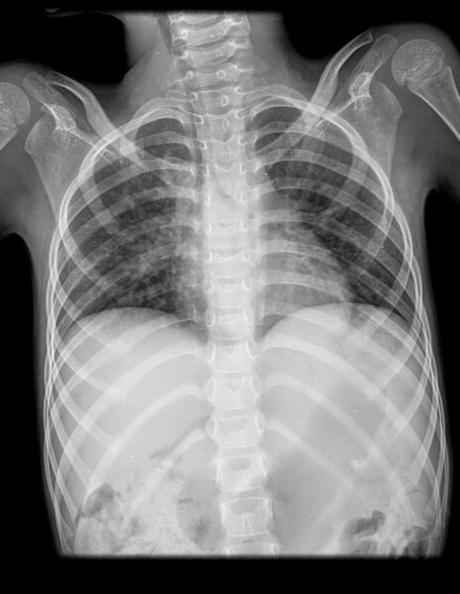

Se observa radiografía posteroanterior de tórax encontrando los siguientes hallazgos:

Los tejidos blandos se muestran con densidad conservada sin aparentes lesiones.

Tejido óseo muestra con adecuada densidad de manera generalizada, sin evidencia de lesiones líticas, blasticas, degenerativas o traumáticas, los arcos costales sin aumento o disminución de sus espacios intercostales, columna dorsal se muestra central con espacios intervertebrales aparentemente conservados. Ambas clavículas centrales.

Los ángulos costodiafragmaticos y cardiofrenicos se muestran libres sin lesiones demostrables.

Hemidiafragmas en situación habitual, sin lesiones aparentes.

El parénquima pulmonar se observa discreto aumento de la radiodensidad pulmonar de aspecto nodular inespecífico como datos incipientes de bronconeumonía.

La tráquea es central y su continuación con los bronquios principales se muestran de calibre y trayectorias habituales y permeables.

Los hilios se muestran sin lesiones aparentes.

La ventana aortopulmonar se muestra sin dilataciones, el trayecto y el calibre aórtico se encuentra conservado.

La silueta cardiaca se muestra sin aumento de sus cavidades de características aparentemente normal.

En abdomen se muestra gas con distribución habitual en estómago.

IMPRESIÓN RADIOLOGICA:

DISCRETO AUMENTO DE LA RADIODENSIDAD PULMONAR DERECHA COMO DATOS INCIPIENTES DE BRONCONEUMONIA CORRELACIONAR CON DATOS CLINICOS.